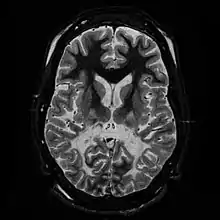

| White matter, with reduced volume and increased signal intensity. The anterior white matter is spared. Features are consistent with X-linked adrenoleukodystrophy. | |